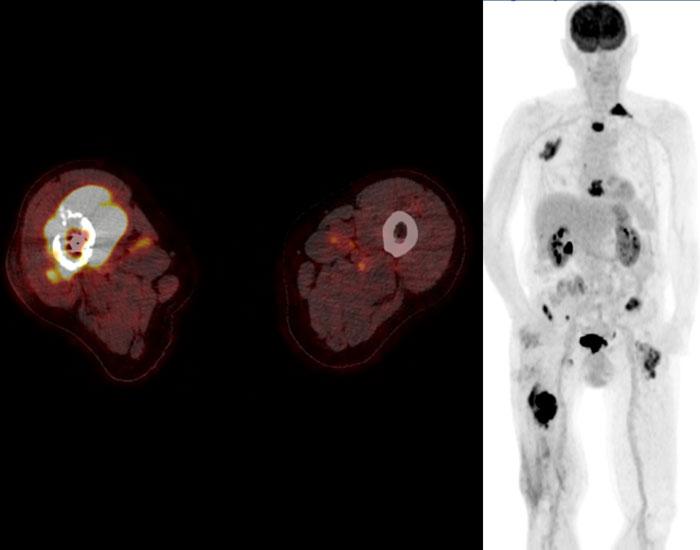

Chúng tôi đã thảo luận trước đây rằng 18F-FDG PET-CT không được khuyến cáo cho u sụn ác tính để phân biệt giữa khối u sụn không điển hình và các khối u độ cao.

Tuy nhiên, trong ung thư sụn dạng biệt hóa,

PET CT kết hợp với CT chẩn đoán lồng ngực có thể được thực hiện để tìm kiếm bệnh di căn.

Ung thư sụn dạng biệt hóa ở xương đùi phải cho thấy độ bắt giữ FDG cao và hình ảnh toàn thân cho thấy nhiều di căn xương ở xương đùi trái, xương đòn trái, các xương sườn trên bên phải và xương ức.

Di căn hạch bạch huyết cạnh chậu hiện diện ở cả hai bên.

Do chondrosarcoma không nhạy cảm với xạ trị và hóa trị, bệnh nhân được điều trị giảm nhẹ, bao gồm đóng đinh xương đùi phải để phòng ngừa gãy xương.

Thật không may, bệnh nhân đã phát triển gãy xương bệnh lý ở xương đùi trái và sau đó đã được điều trị.

Hình ảnh CT ngực theo mặt phẳng coronal cho thấy khối mô mềm xung quanh

ổ di căn tại xương đòn trái.

Không phát hiện di căn phổi.

Tiên lượng của u sụn dạng biệt hóa kém rất xấu với tỷ lệ sống còn toàn bộ 5 năm khoảng 18%.